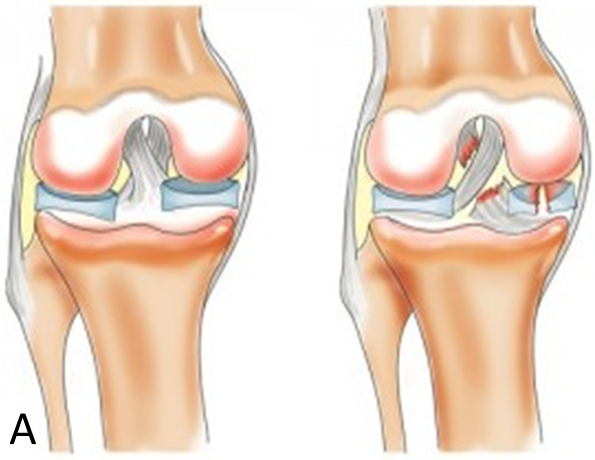

Запитання 11

РОЗПІЗНАЙТЕ ДОДАТКОВІ ЕЛЕМЕНТИ ЦЬОГО СПОЛУЧЕННЯ.

варіанти відповідей

ДИСКИ

МЕНІСКИ

СУМКИ

БУРСИ

ЗВ'ЯЗКИ